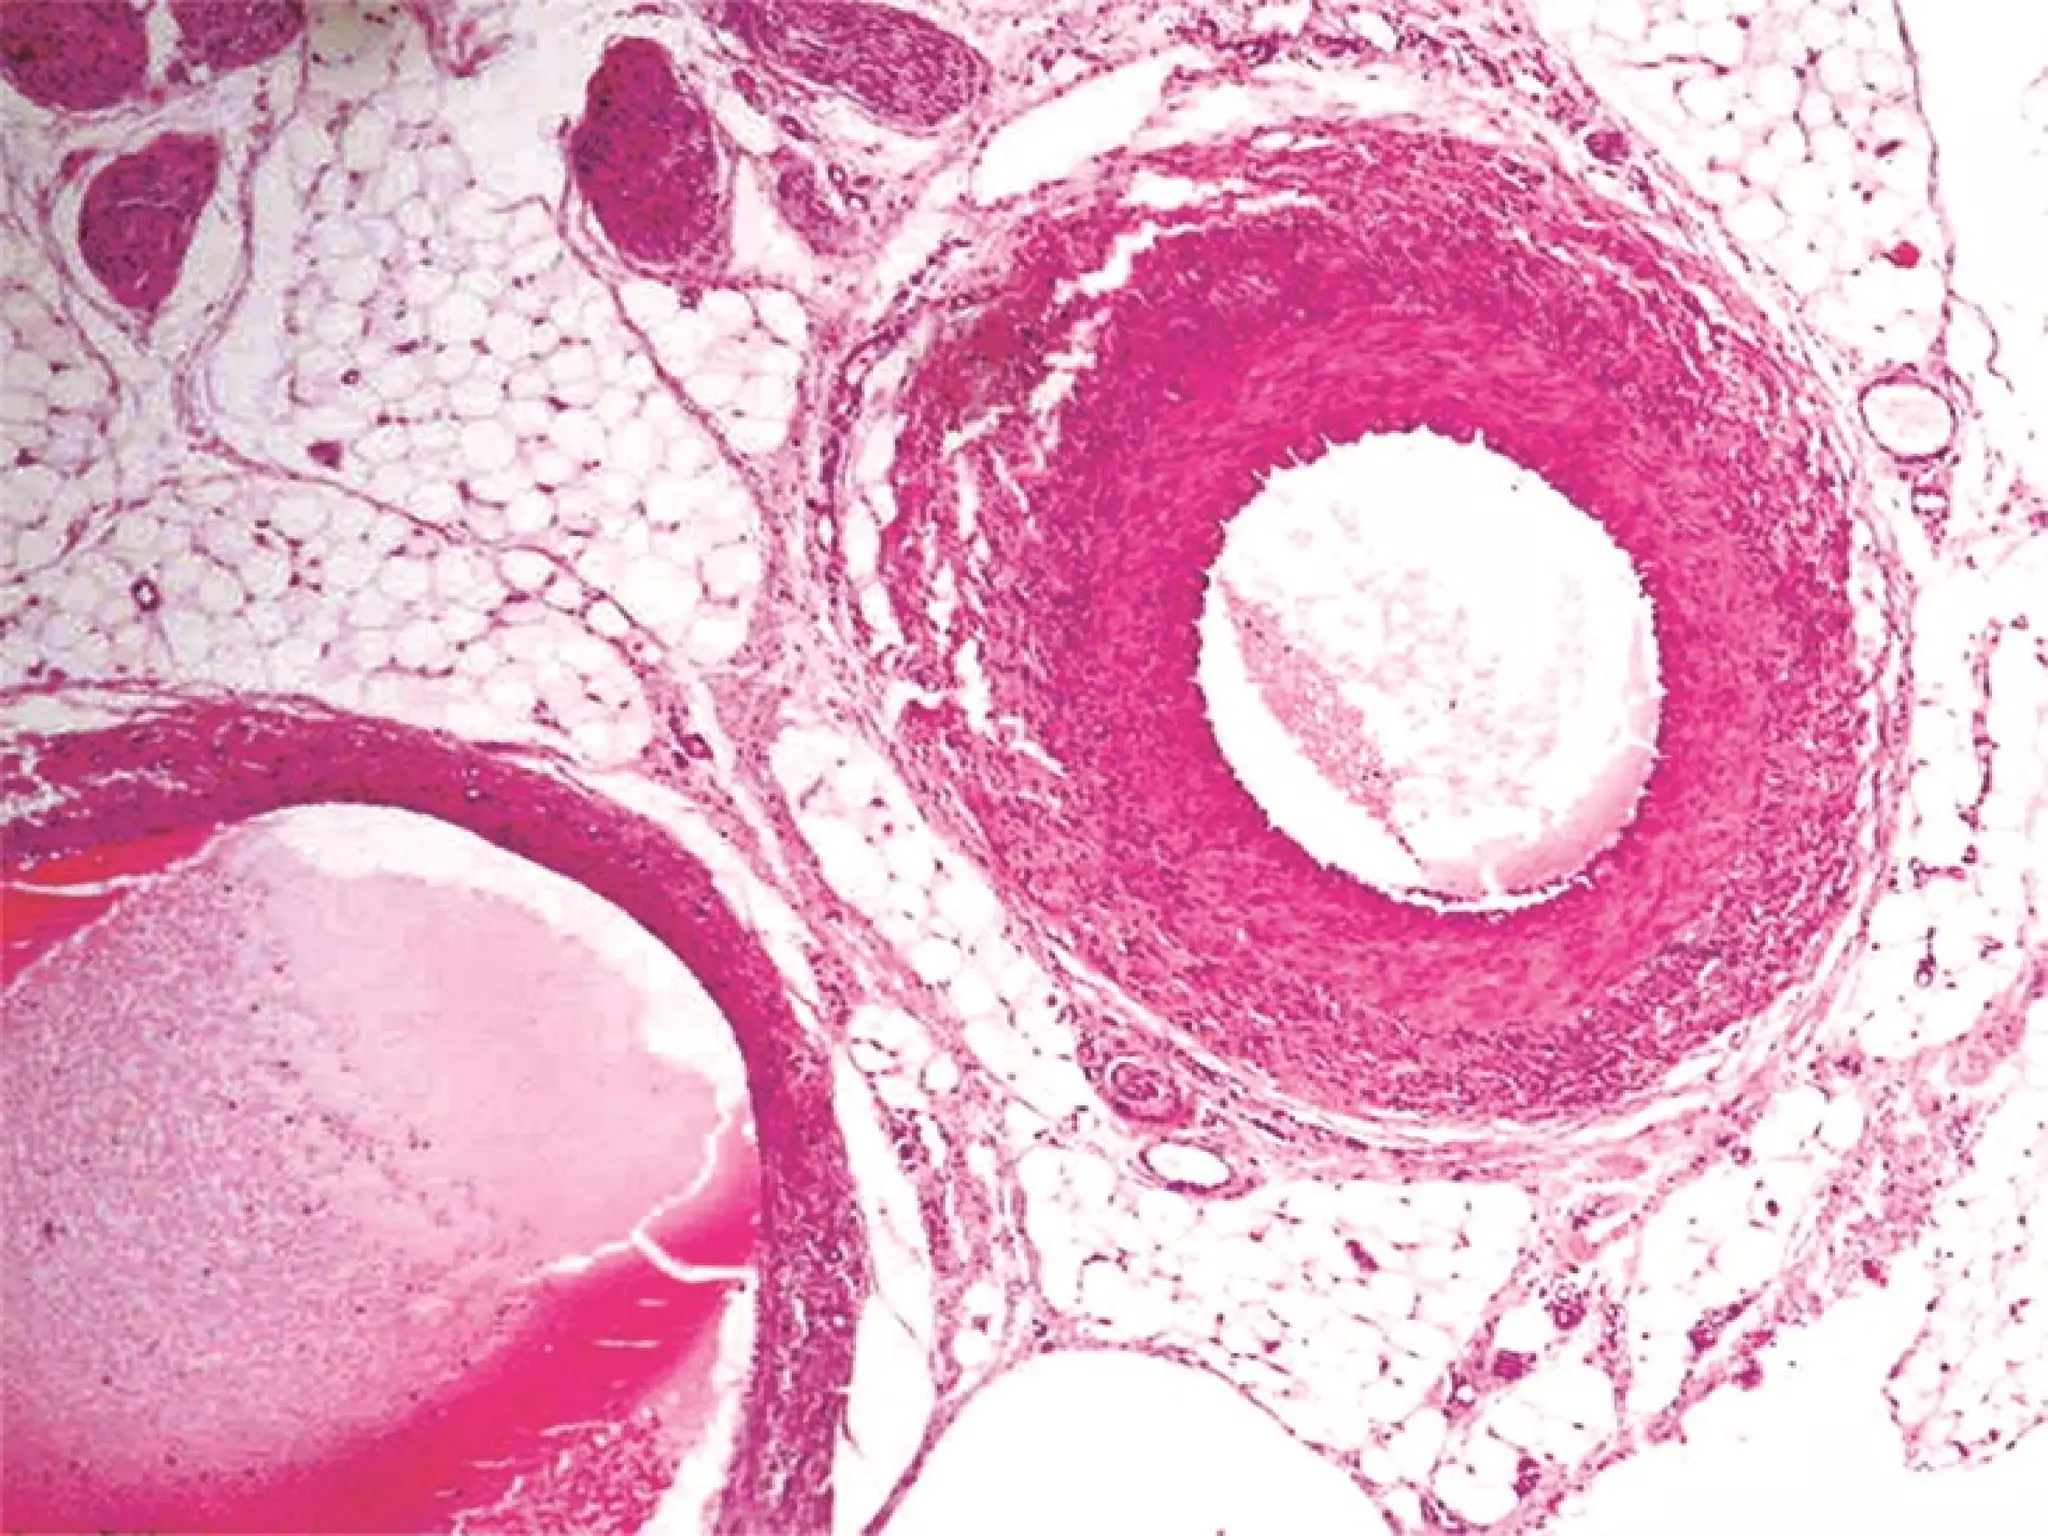

This document outlines several human body systems including the vascular, lymphatic, respiratory, digestive, and endocrine systems. It describes the trachea and lungs in the respiratory system, the oral cavity and digestive glands in the digestive system, and mentions the parotid, pancreas, and classic hepatic lobule in relation to the digestive system and endocrine glands.